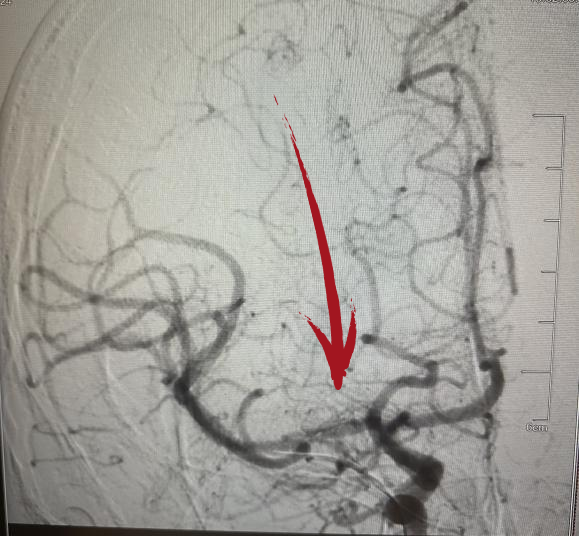

▲术前DSA右侧大脑中动脉起始段闭塞

▲术后DSA提示右侧大脑中动脉已开通